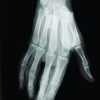

The patient first noticed the presence of the painless nodules 3 months before presentation. No impairment in the usual activities of daily living or in sports activities was reported. Physical examination at the time revealed symmetrical, non-tender swelling involving the PIP joint, with no limitation or tenderness with active and passive range of motion. The patient had already undergone evaluation by serology for inflammatory and connective tissue diseases that turned out negative. We recommended plain X-rays (Fig. 2) and magnetic resonance imaging (Fig. 3) for further evaluation. Both studies came out revealing no osseous or soft tissue malignancy; also, no radiological evidence of an inflammatory process involving the synovium, the ligaments, the tendons, and the subcutaneous tissues was present. No tissues were sent to the pathology due to the diagnosis being clear.